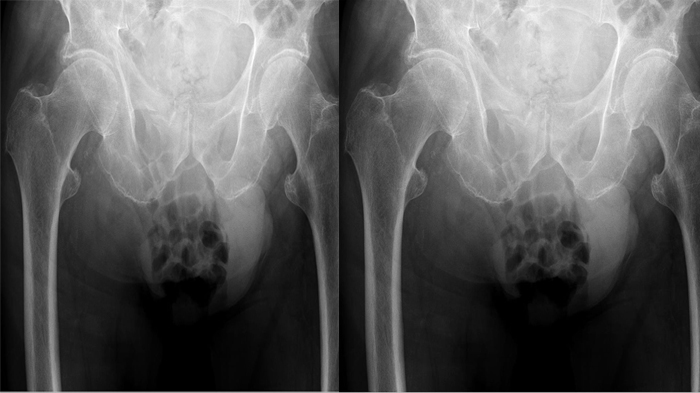

Satu diantara organ reproduksi pria ini tiba-tiba membengkak, ukurannya sebesar buah kelapa.

Buah zakar yang membengkak itu beratnya mencapai 2kg dan berada di selangkangannya.

“Benjolan itu kini menjadi beban, saya sulit untuk bergerak dan bila dipencet benjolan itu akan menjadi keras," katanya.